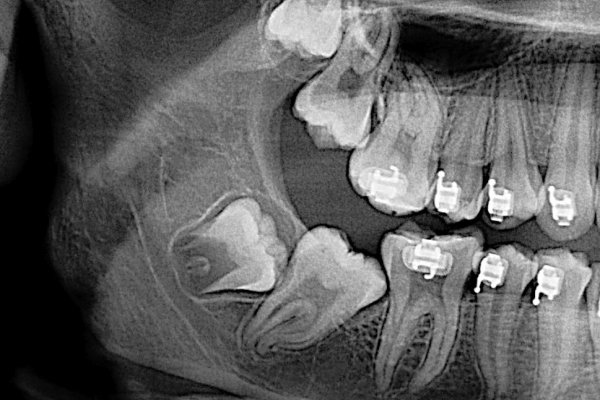

사람의 악골(턱뼈)은 점차 작아지는데, 이때문에 사랑니가 잇몸 밖으로 완전히 나오지 못하고 뼈속에 뭍히는 경우 매복치라고 합니다. 매복치나 불완전한 사랑니로 잇몸에 염증이 생겨 붓고 아픈 현상을 지치주위염이라고 합니다. 지치주위염이 심할 경우 염증치료 및 약물복용을 통해 염증 완화 후 발치합니다.

매복치

지치주위염